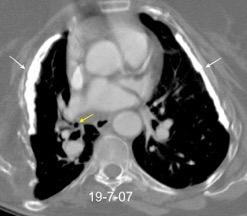

Tromboembolismo pulmonar.

Frecuencia del derrame:

Rx: 32%. TC: 47%

Unilateral. 85%

< 1/3 del hemitórax: 90%

Todos exudados

58% con eritrocitos

21% tabicación lo que causa demora en el diagnóstico

TEP. Empiema pleural. Atelectasia redonda

Porcel JM et al. Analysis of pleural effusions in acute pulmonary embolism: radiological and pleural fluid data from 230 patients. Respirology 2007/ Iguchi T et al. Desquamation of the subpleural lung parenchyma caused by empyema after pulmonary embolism: A case report. Respirol Case Rep. 2022 .